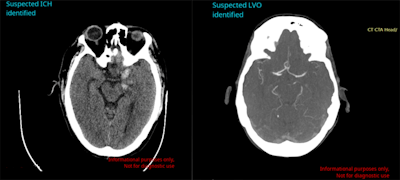

Within 20 seconds, Cina Head can automatically detect and alert radiologists to the presence of intracranial hemorrhage (ICH) and large-vessel occlusion (LVO) on CT scans of emergency room patients, according to the vendor. Radiologists are notified of these findings within their existing systems and workflow, Avicenna.ai said.

In testing on data from 814 cases at more than 250 imaging centers in the U.S., the software yielded 91.4% sensitivity, 97.5% specificity, and 96% accuracy for detecting ICH, the company said. Cina Head delivered 97.9% sensitivity, 97.6% specificity, and 97.7% accuracy for detecting LVO on 476 cases.